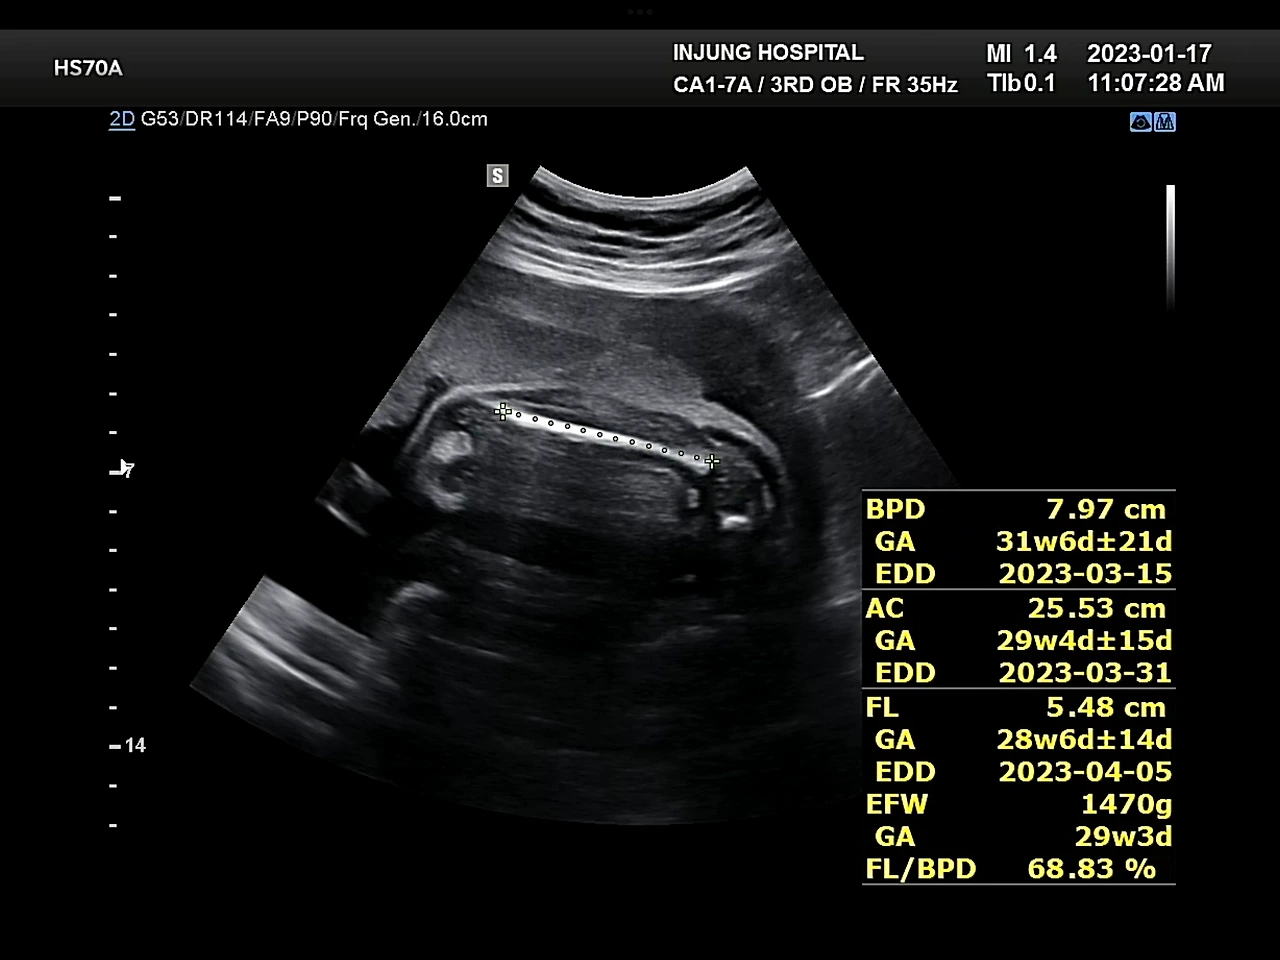

왼: 코 짜부짜부 / 오: 포도는 1.47kg

지금껏 아이가 주수보다 1주 정도 크니, 체중조절을 하라는 말을 들어왔는데, 29주 검사에서 아이가 주수에 맞게 크고 있다며 체중조절을 잘한 것 같다는 이야길 들었다. 사실 평소처럼 잘 먹고 지내서 찔리긴 했지만, 포도가 잘 자라고 있다는 말은 언제 들어도 좋은 소식이다. 진료를 마치고 예진실에서 후기 임산부 교육이 있었다. 이제 굵직한 검사들은 다 끝났다는 말이 안심이 되었다. 좋은 소식이 많았던 하루.